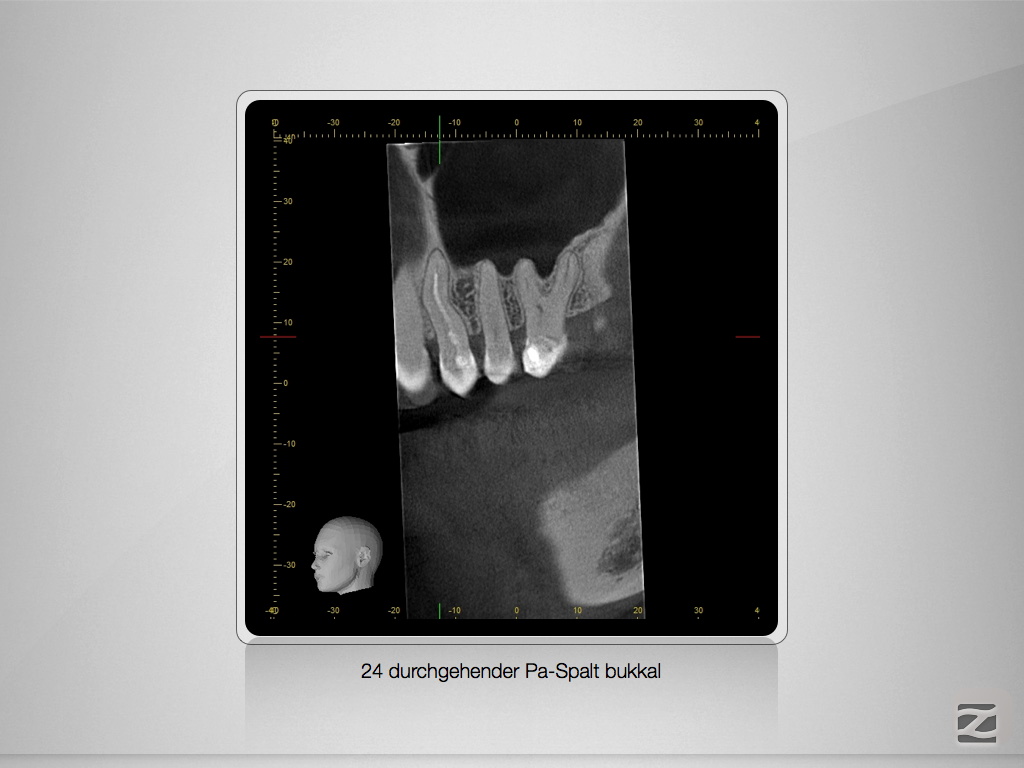

2D vs. 3D – So habe ich entschieden